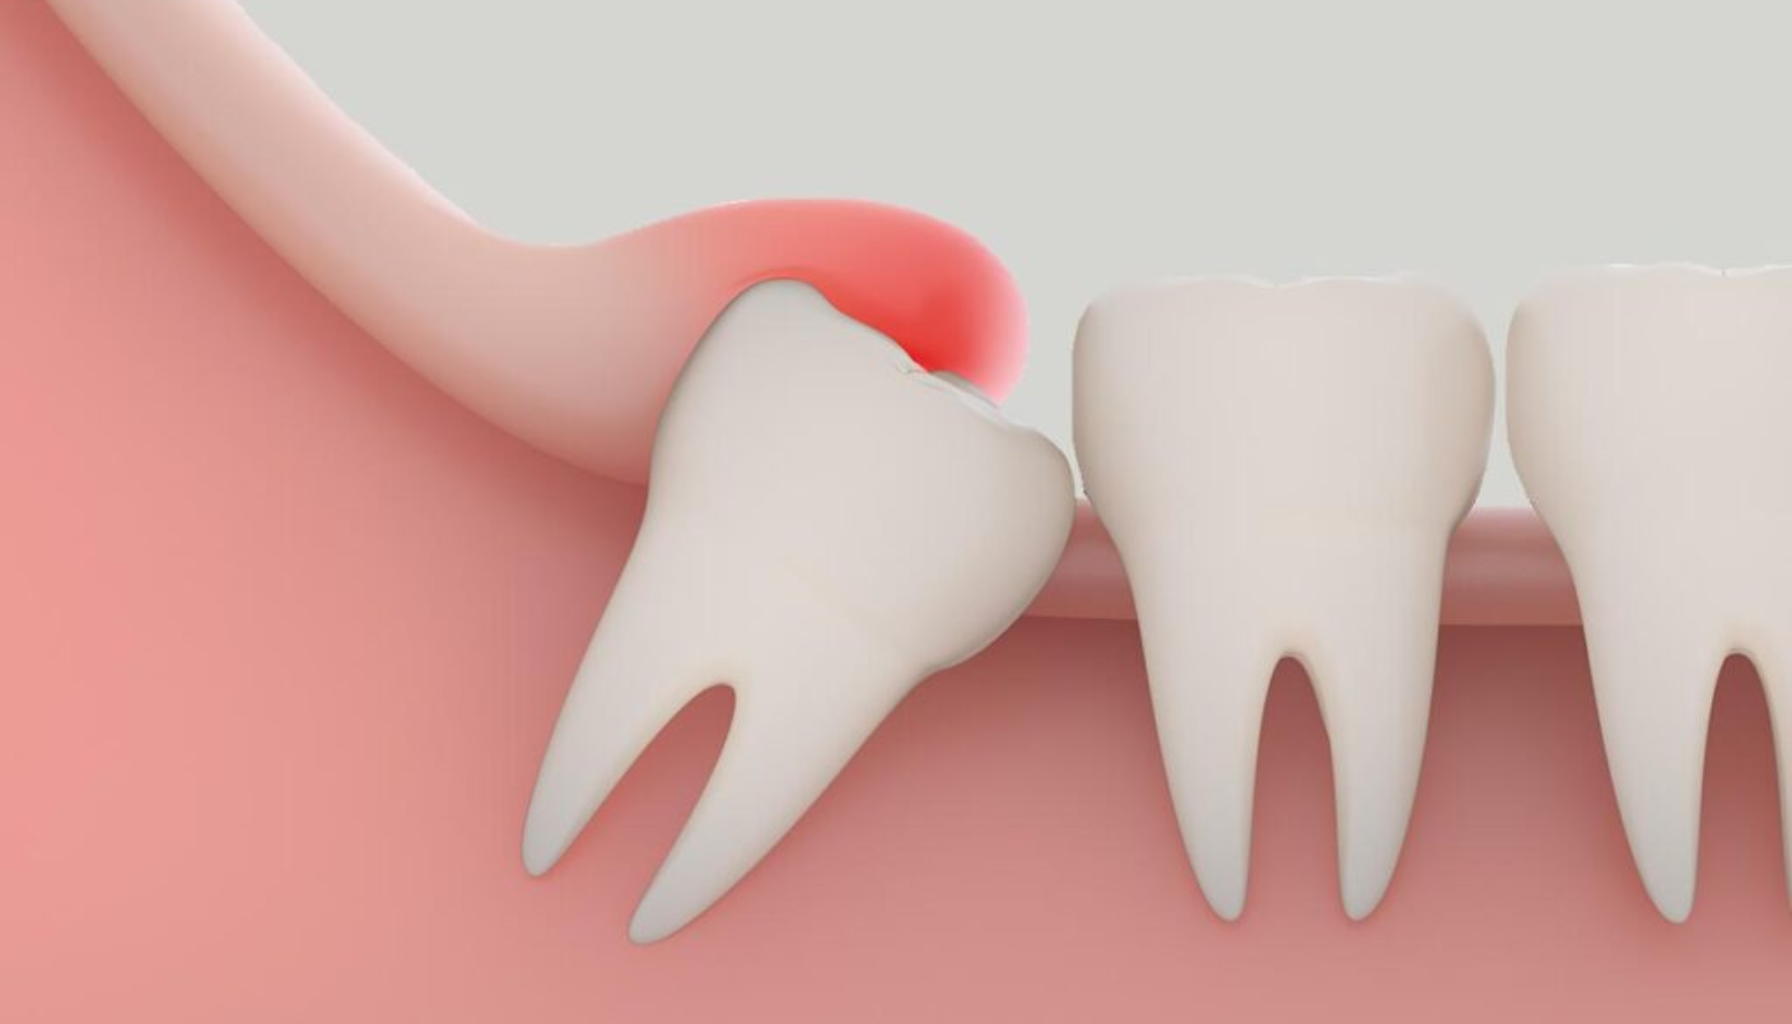

Perikoronitt er en betennelse i vevet som omgir en visdomstann som ikke har kommet helt frem. Når tannen delvis bryter gjennom tannkjøttet, skapes det en liten lomme der bakterier lett kan samle seg. Denne lommen er vanskelig å holde ren, og resultatet kan bli infeksjon og betennelse.

Kort forklart: perikoronitt er en lokal tannkjøttsinfeksjon som oppstår fordi visdomstannen ikke får nok plass til å bryte frem, og dermed skaper et miljø hvor bakterier trives.

- Årsak: Betennelsen oppstår når en visdomstann bare delvis bryter frem, noe som skaper et hulrom hvor bakterier lett samler seg.